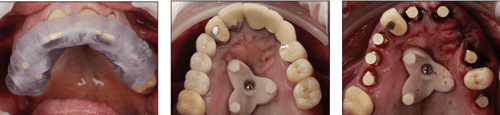

Pre-op STL file, Diagnostic design, Archived design

During surgery, the S.I.M. device enabled accurate intraoral data capture without photogrammetry or traditional chairside processing.

S.I.M. fixation guide S.I.M. device, seated Implant scan ready